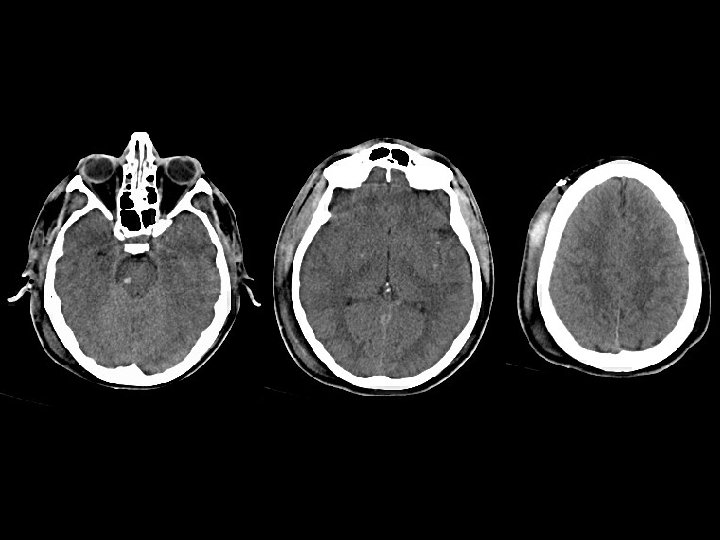

Diffuse Axonal Injury • Findings: – Diffuse brain swelling – Focal punctate hemorrhage scattered in the white matter, corpus callosum, and brain stem – Right subgaleal hematoma • Due to diffuse shearing injury, sudden deceleration (MVA) • MRI findings: – Hemorrhage best seen on GRE sequence